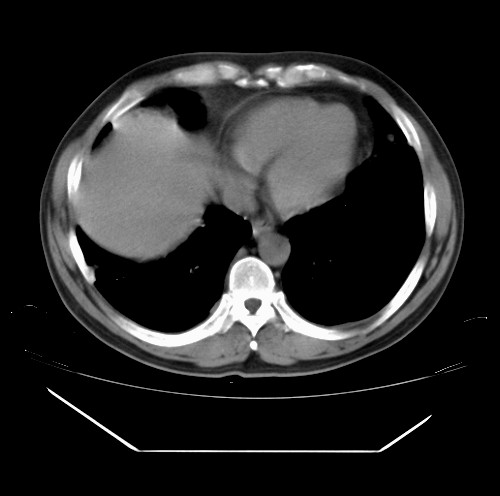

标题: CT22085:双肺多发结节

男,44岁,咳嗽,痰中带血2天。

病灶大部分位于胸膜下,结节大小相差不是很大,肺尖太干净。这种结核没见过,我认为可排除。

首先考虑转移,不除外肉芽肿、真菌感染。建议查其它。

除肺内及胸膜下可见多发大结节外,在肺小叶中心核、小叶间隔及支气管血管束上亦可见多方小结节,可以认为是随机分布。考虑转移可能性大。

仔细观察病灶形态,病灶边界部分清楚,结合临床症状,首先考虑转移,纵隔内多个肿大淋巴结影。

双肺血管纹理末端多发类圆形结节,边界光滑清晰 气管前腔静脉后淋巴结肿大

考虑转移瘤

本例双肺多发类圆形高密度灶,边清,结合病史多考虑双肺多发转移改变,可以结合实验室检查。